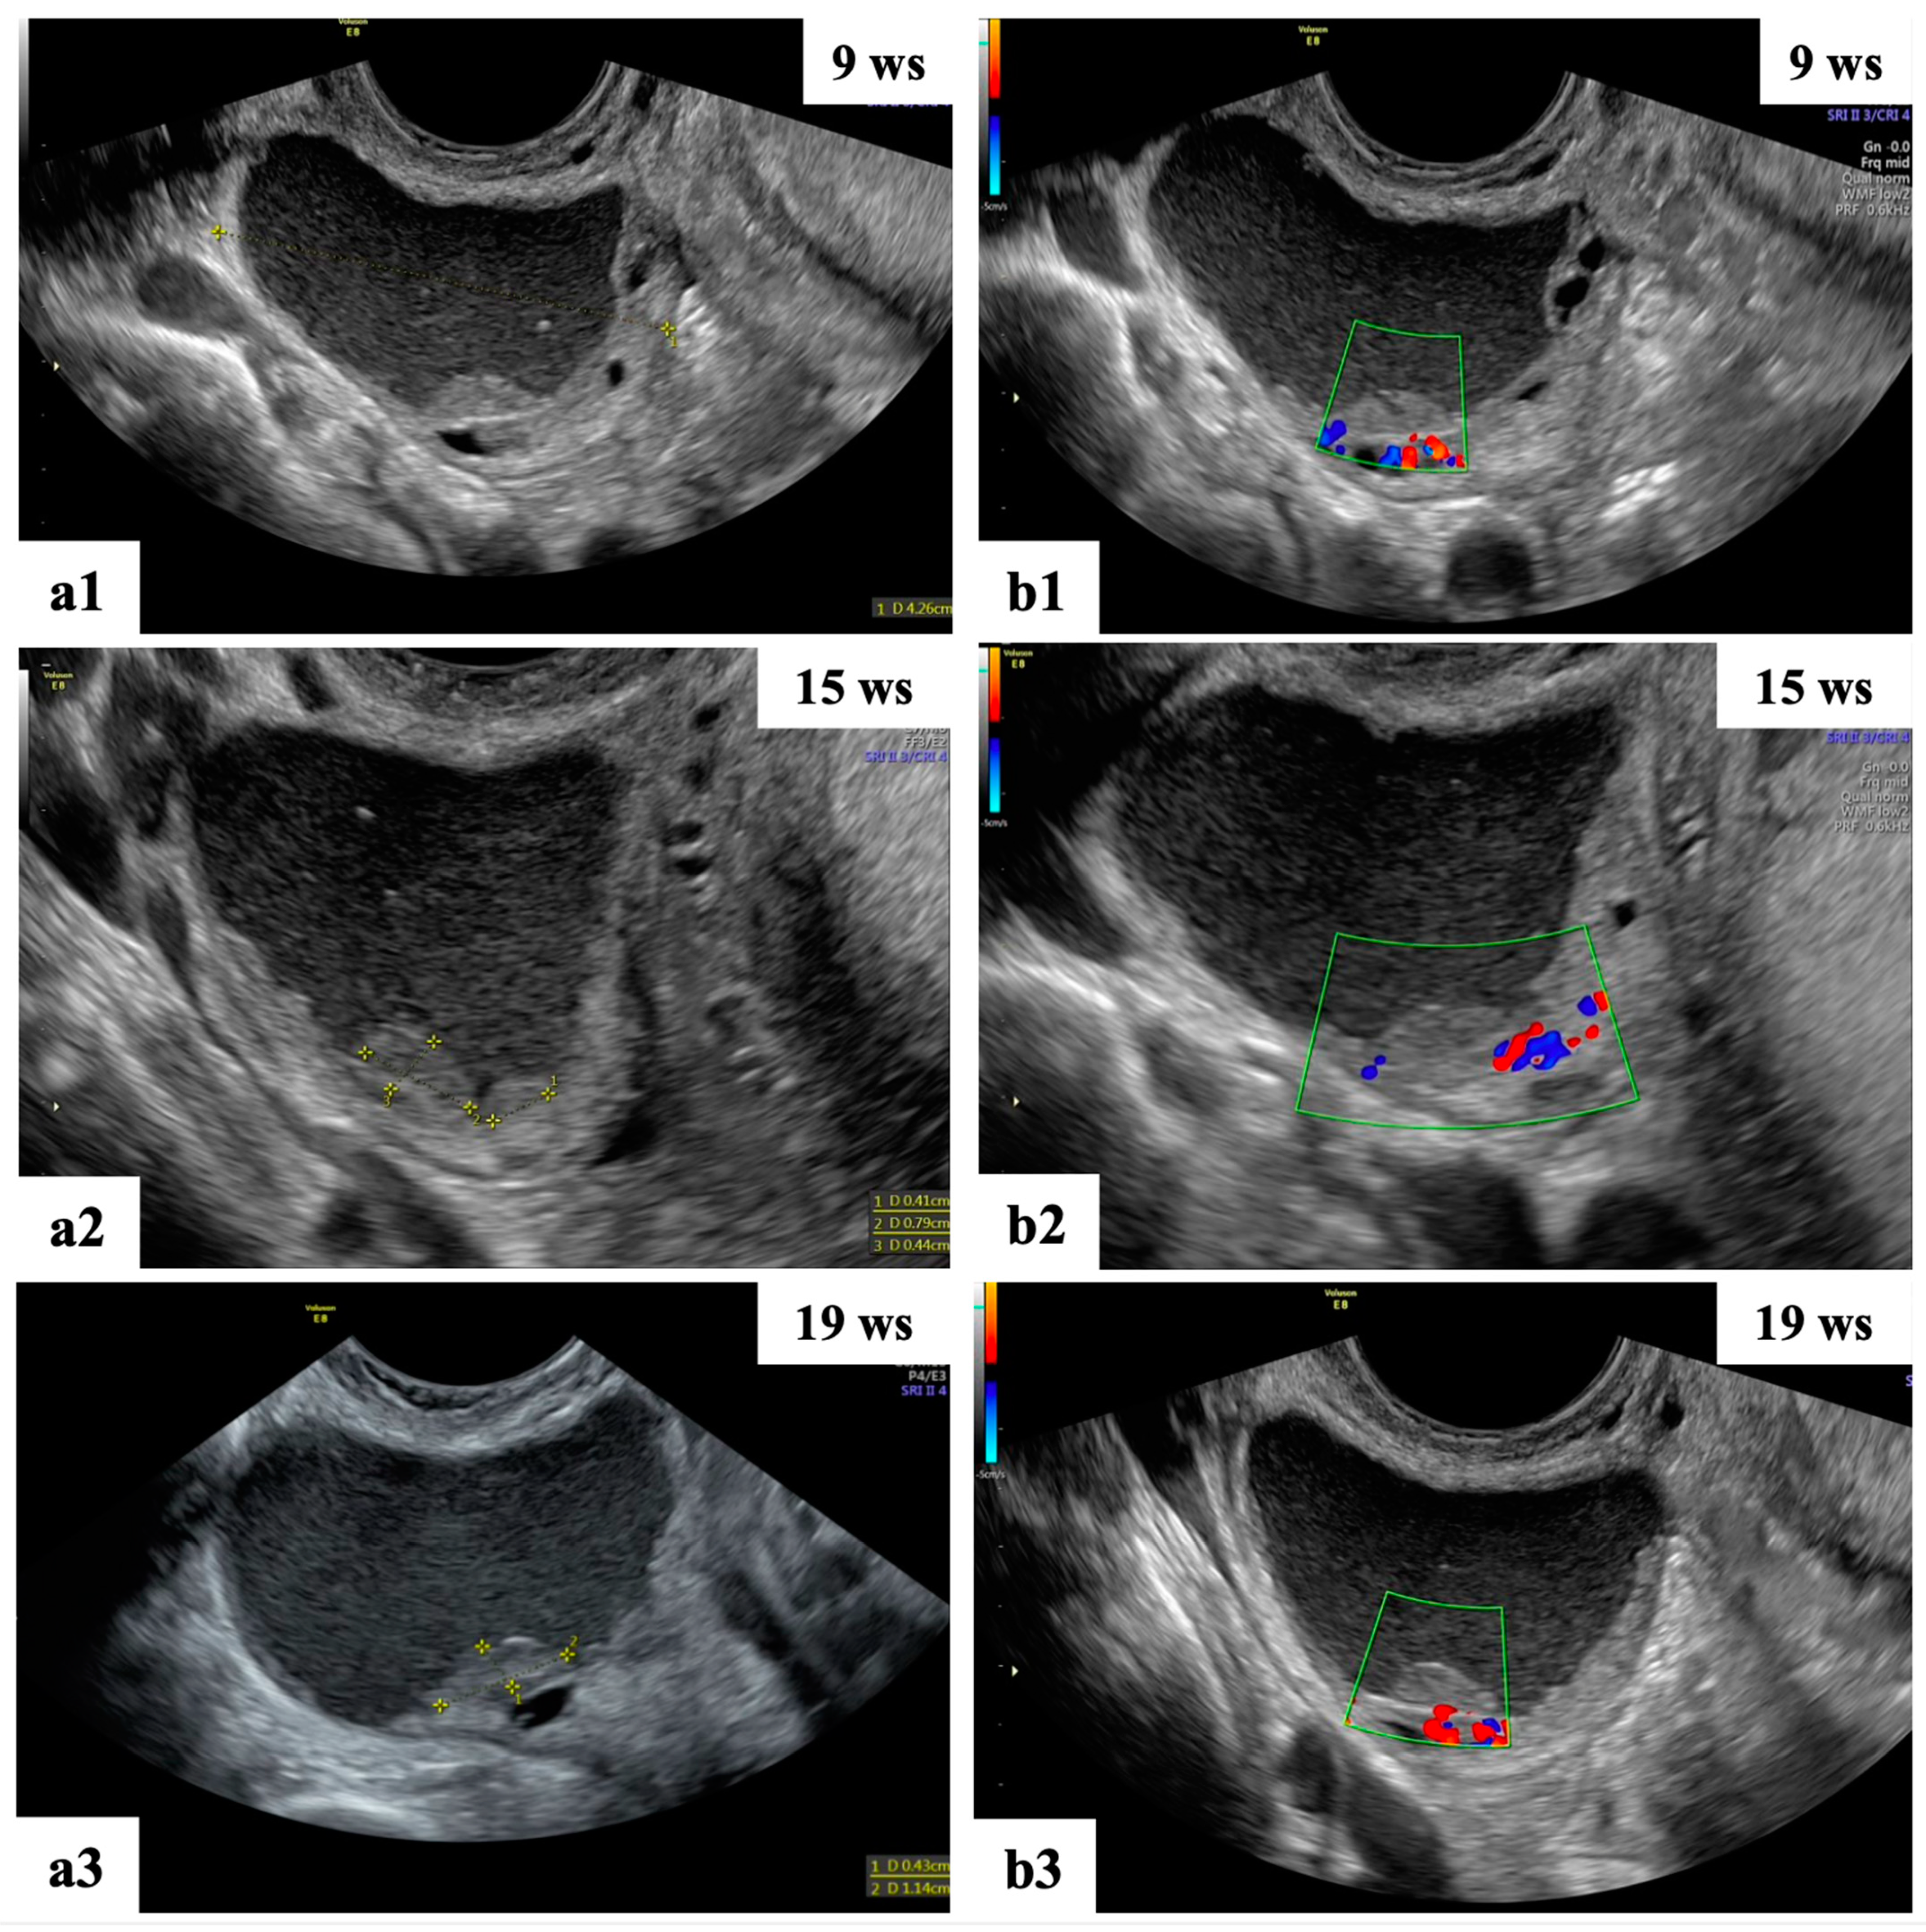

- Mascilini, F.; Moruzzi, C.; Giansiracusa, C.; Guastafierro, F.; Savelli, L.; De Meis, L.; Epstein, E.; Timor-Tritsch, I.E.; Mailath-Pokorny, M.; Ercoli, A.; et al. Imaging in gynecological disease. 10: Clinical and ultrasound characteristics of decidualized endometriomas surgically removed during pregnancy. Ultrasound Obstet. Gynecol. 2014, 44, 354–360. [Google Scholar] [CrossRef]

- Moro, F.; Mascilini, F.; Pasciuto, T.; Leombroni, M.; Li Destri, M.; De Blasis, I.; Garofalo, S.; Scambia, G.; Testa, A.C. Ultrasound features and clinical outcome of patients with malignant ovarian masses diagnosed during pregnancy: Experience of a gynecological oncology ultrasound center. Int. J. Gynecol. Cancer 2019, 29, 1182–1194. [Google Scholar] [CrossRef]

| Papillation flow Present Absent | 2/4 2/4 |

| Height of the largest papillary projection (mm) (range) | 7.5 (3–13) |